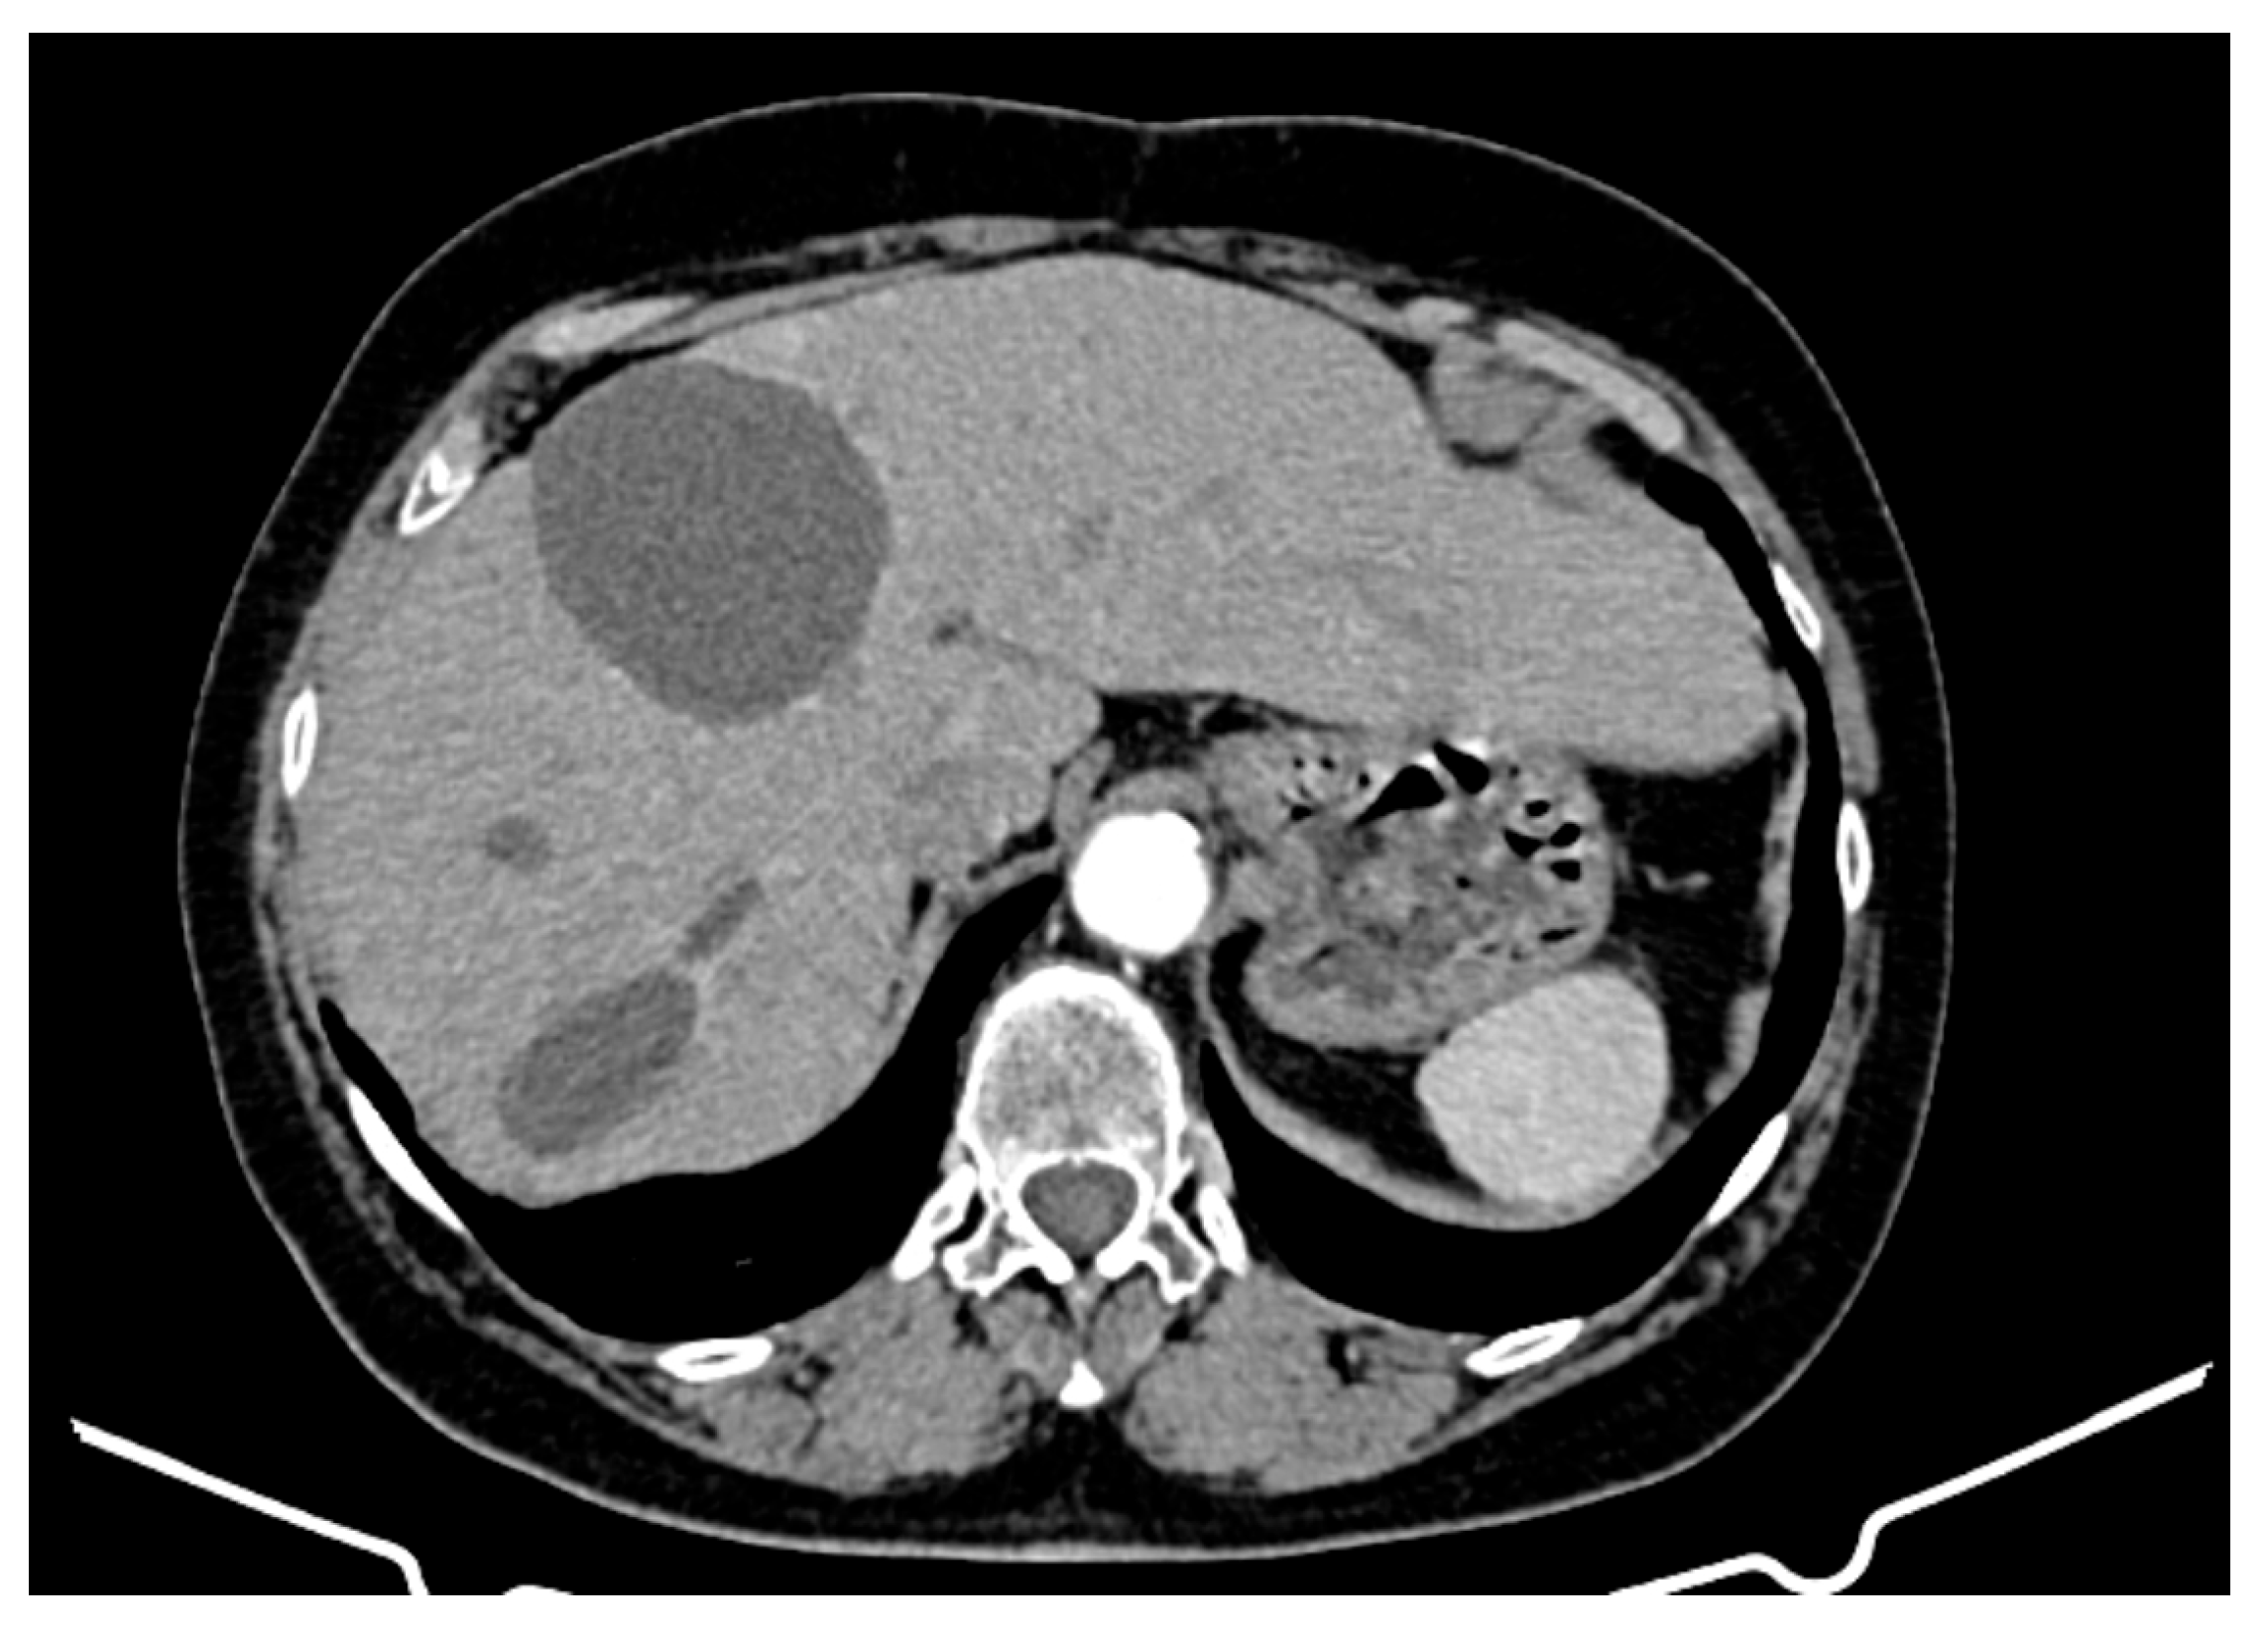

- Hepatic tumour stability: Multiple large cystic hepatic lesions remained stable in size throughout the monitoring period, with no significant new secondary lesions developing. The largest hepatic cystic tumours persisted in segments IV, VI, and VIII, with maximum dimensions of ~8 cm, without major structural changes.

- New large cystic tumour formation;

- Previously known lesions remaining stable;

- An absence of metastatic progression.

- Procedure: Addressed cystic tumour in the left hepatic lobe.

- Procedure: Atypical segment III hepatectomy for a large cystic tumour.